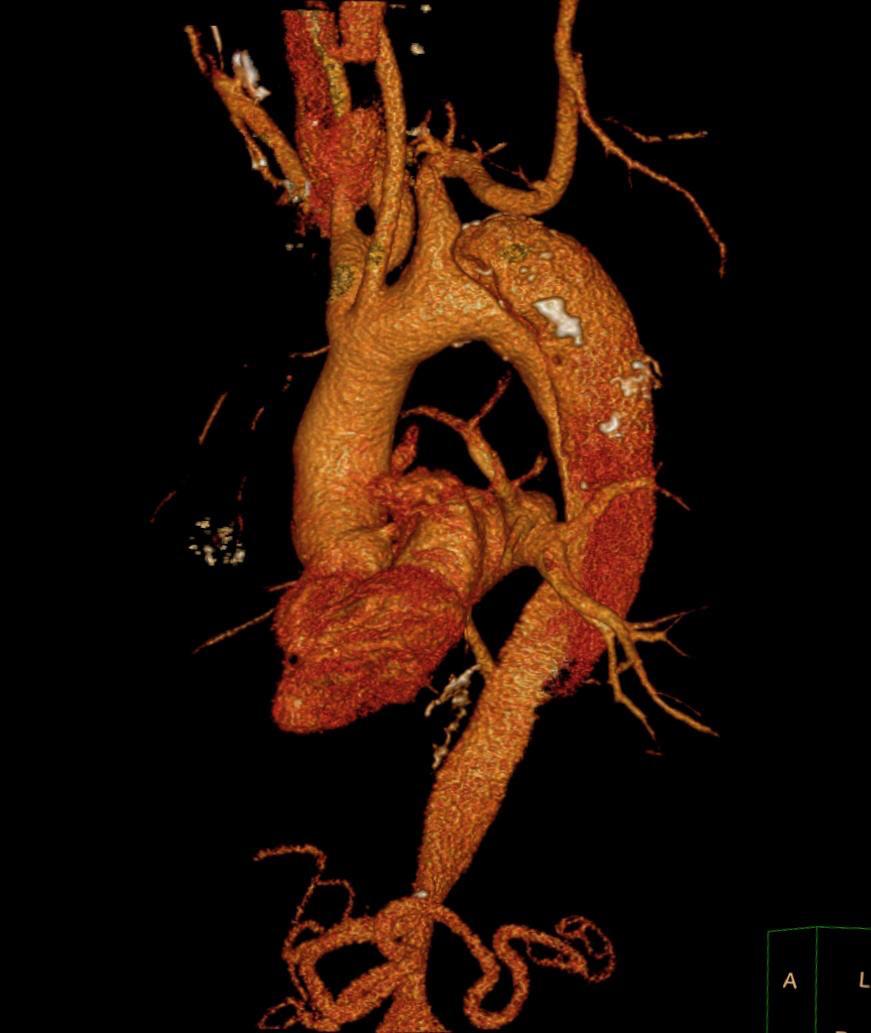

كانت مستشفيات جامعة أسيوط قد استقبلت مريضا يبلغ من العمر 60 عاما، يعاني من انشطار بالشريان الأورطي من النوع (ب) مع تجمع دموي ممتد إلى الشرايين المغذية للمخ، وهي حالة عالية الخطورة، ليقوم الفريق الطبي بإجرائها على مرحلتين، حيث تضمنت المرحلة الأولى التدخل الجراحي، وفورا تم التنسيق مع مستشفى القلب تحت إشراف الدكتور محمد عياد مدير المستشفى، وتم تشكيل فريق طبى برئاسة الدكتور هيثم علي حسن، أستاذ ورئيس قسم جراحة الأوعية الدموية، والدكتور أحمد إبراهيم، مدرس جراحة القلب والصدر، وضم كلا من: الطبيب عمرو محمد ممدوح، مدرس مساعد بقسم جراحة القلب والصدر، والطبيب محمد هشام القاضى، مدرس مساعد بقسم جراحة الأوعية الدموية، والطبيب عبدالرحمن شوقي الطوخى، مدرس مساعد بقسم جراحة الأوعية الدموية.

وأجرى الفريق الطبي بجامعة أسيوط عملية جراحية استمرت لمدة 4 ساعات، حيث قاموا بإعادة توصيل فروع الشريان الأورطي جراحيًا باستخدام وصلات شريانية صناعية إلى شرايين المخ وشرايين الطرفين العلويين، وقد وفرت هذه الخطوة منطقة هبوط آمنة ودعمت استمرار التروية للمخ والطرفين العلويين، وهو ما كان ضروريا قبل الانتقال للمرحلة الثانية.

بينما تضمنت المرحلة الثانية استخدام القسطرة التداخلية بعد تخطيط دقيق وتنسيق وثيق بين التخصصات المختلفة، حيث قام الفريق الطبي بقسم جراحة الأوعية الدموية بالمستشفى الجامعى الرئيسى تحت إشراف الدكتور خالد عبد العزيز مدير المستشفى، وبرئاسة الدكتور هيثم علي حسن رئيس القسم، وضم كلا من: الدكتور محمود إسماعيل، أستاذ جراحة الأوعية الدموية، والطبيب أحمد نجيب، مدرس مساعد بالقسم، بإجراء إصلاح للانشطار بالشريان الأورطي الصدري والبطني باستخدام القسطرة التداخلية وتركيب دعامات مغطاة باستخدام تقنية (TEVAR).